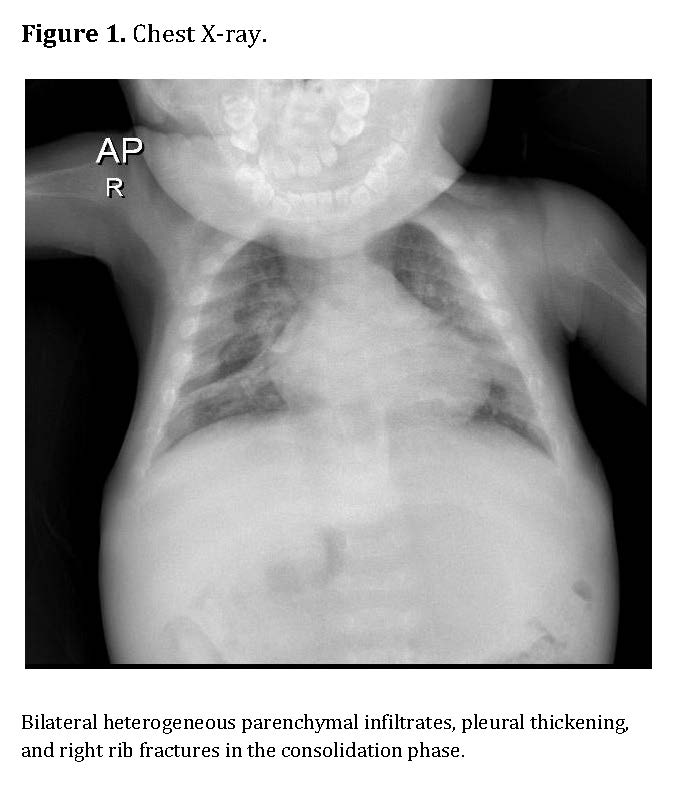

Chest radiography showed bilateral heterogeneous parenchymal infiltrates, pleural thickening, and right-sided rib fractures in the consolidation phase (Figure 1). Radiographs of long bones revealed severe osteopenia, periosteal reaction, and multiple pathological fractures, including the right and left humerus, right ulna, and right femur (Figures 2 and 3).